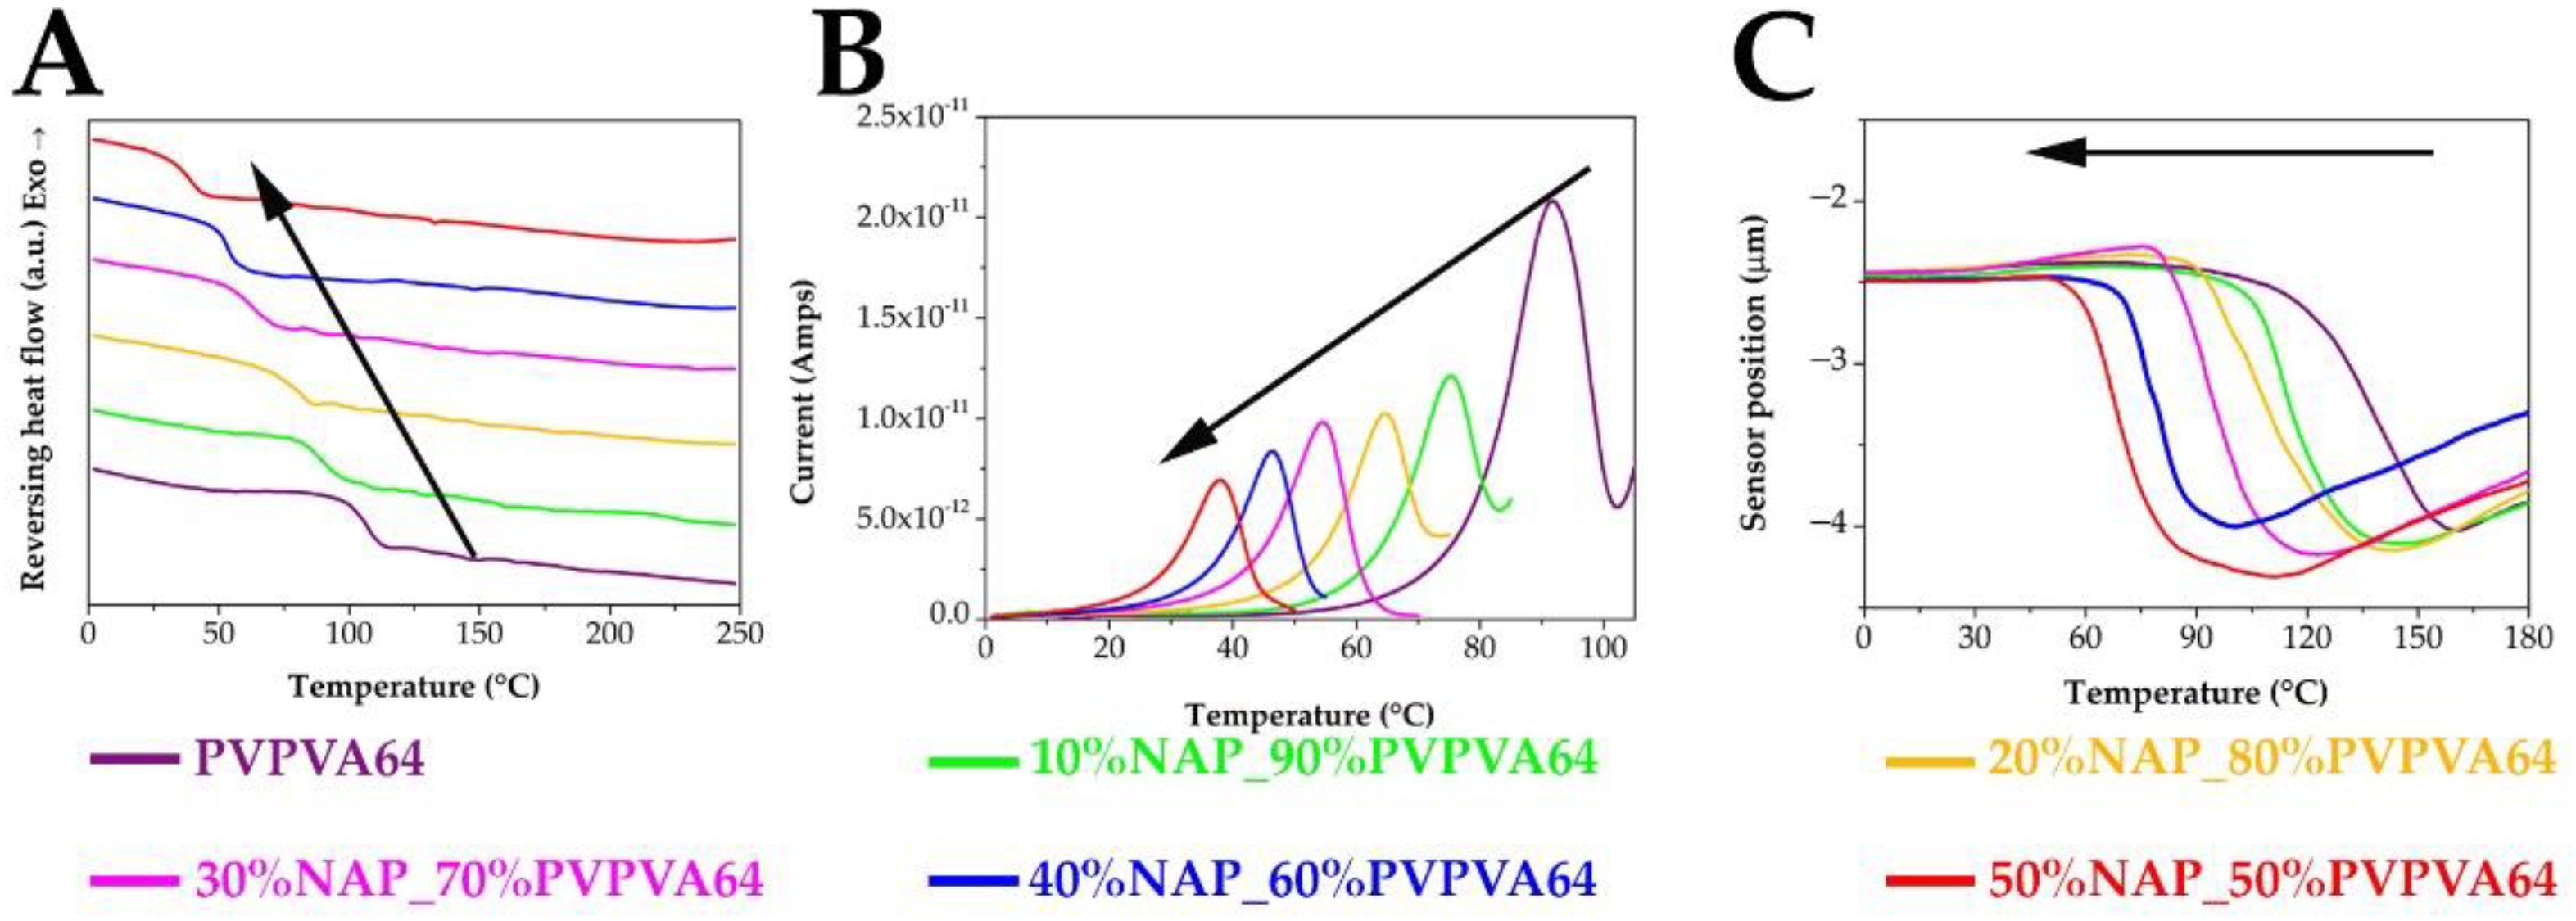

3.2. Measuring the Glass Transition Temperature with Different Methods

3.3. Effect of the Stress Stability Tests

3.4. Correlations between the Measured Tg Values and the Stability